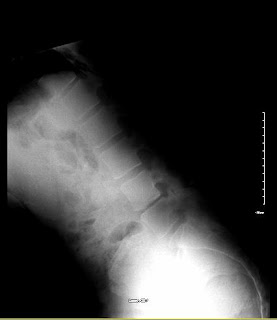

Had my 2 year follow up with MRI and X-ray's last week and I have posted the images below. The surgeon (Dr V) was surprised that the L4 and L5 bones showed signs of improved health ( 2 years ago they both took a beating from the wear and tear on them). The disc is still degenerating but it's seems to have slowed somewhat.

I think the Wallis system is a long term fix for me - having that support and 'gap' between L4 and L5 will ensure the rate of demise of my back is slowed, but it's not a short term fix.

Below are the MRI and X-Ray images:

(X-Ray courtesy of BCH)